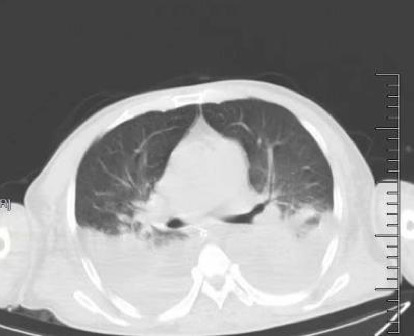

Introduction: Scrub typhus is an acute infectious disease caused by Orientia tsutsugamushi, whose pathophysiology is characterized by systemic small-vessel vasculitis. Its high misdiagnosis rate stems from its nonspecific clinical features. If not diagnosed and treated in time, patients may rapidly progress to multiorgan dysfunction syndrome (MODS) or even disseminated intravascular coagulation (DIC), posing a severe threat to life. Case Presentation: The patient was a 68-year-old male with "recurrent fever and dry cough for six days." He was admitted to the hospital with a diagnosis of scrub typhus. After admission, he developed severe acute respiratory distress syndrome (ARDS), MODS, septic shock, DIC with thrombocytopenia, hypofibrinogenemia, significant hyperfibrinolysis, and myocardial depression. The patient improved following treatment with doxycycline, moxifloxacin, renal replacement therapy, blood transfusion, antifibrinolysis, invasive mechanical ventilation, and other supportive therapies. The patient's coagulation profile in DIC caused by scrub typhus demonstrated significant hyperfibrinolysis, differing from that of garden-variety sepsis, and no similar cases were identified in a search of medical literature/databases. Conclusion: The fibrinolytic system in DIC caused by scrub typhus is excessively active, and antifibrinolytic therapy may benefit such patients. Further research on the distinct coagulation abnormalities in scrub typhus-associated DIC would be highly valuable compared to sepsis-associated DIC.